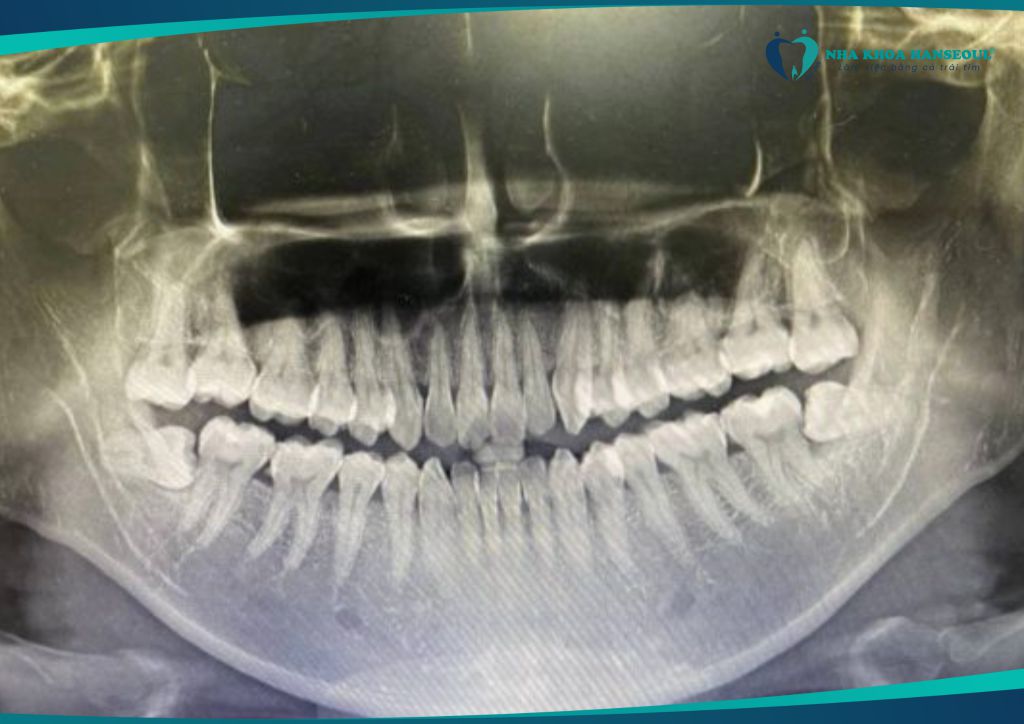

2.3 Chèn ép dây thần kinh – tê môi, cằm

Răng khôn mọc ngầm sâu gần dây thần kinh hàm dưới có thể gây:

- Tê môi, tê cằm một bên

- Dị cảm kéo dài sau viêm

- Có thể tổn thương vĩnh viễn nếu không can thiệp sớm

2.5 Hình thành u nang xương hàm

Răng khôn mọc ngầm có thể bị bao bọc bởi nang dịch. → Lâu ngày hình thành u nang xương hàm, gây:

- Tiêu xương, phá hủy cấu trúc hàm

- Đau nhức sâu

- Phẫu thuật loại bỏ phức tạp

- Chụp phim cho thấy mọc lệch, mọc ngầm, đâm vào răng khác